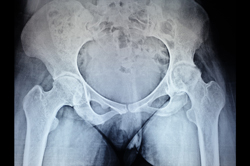

Intertrochanteric Fracture

Neck Femur Fracture

Total Hip Replacement - THR